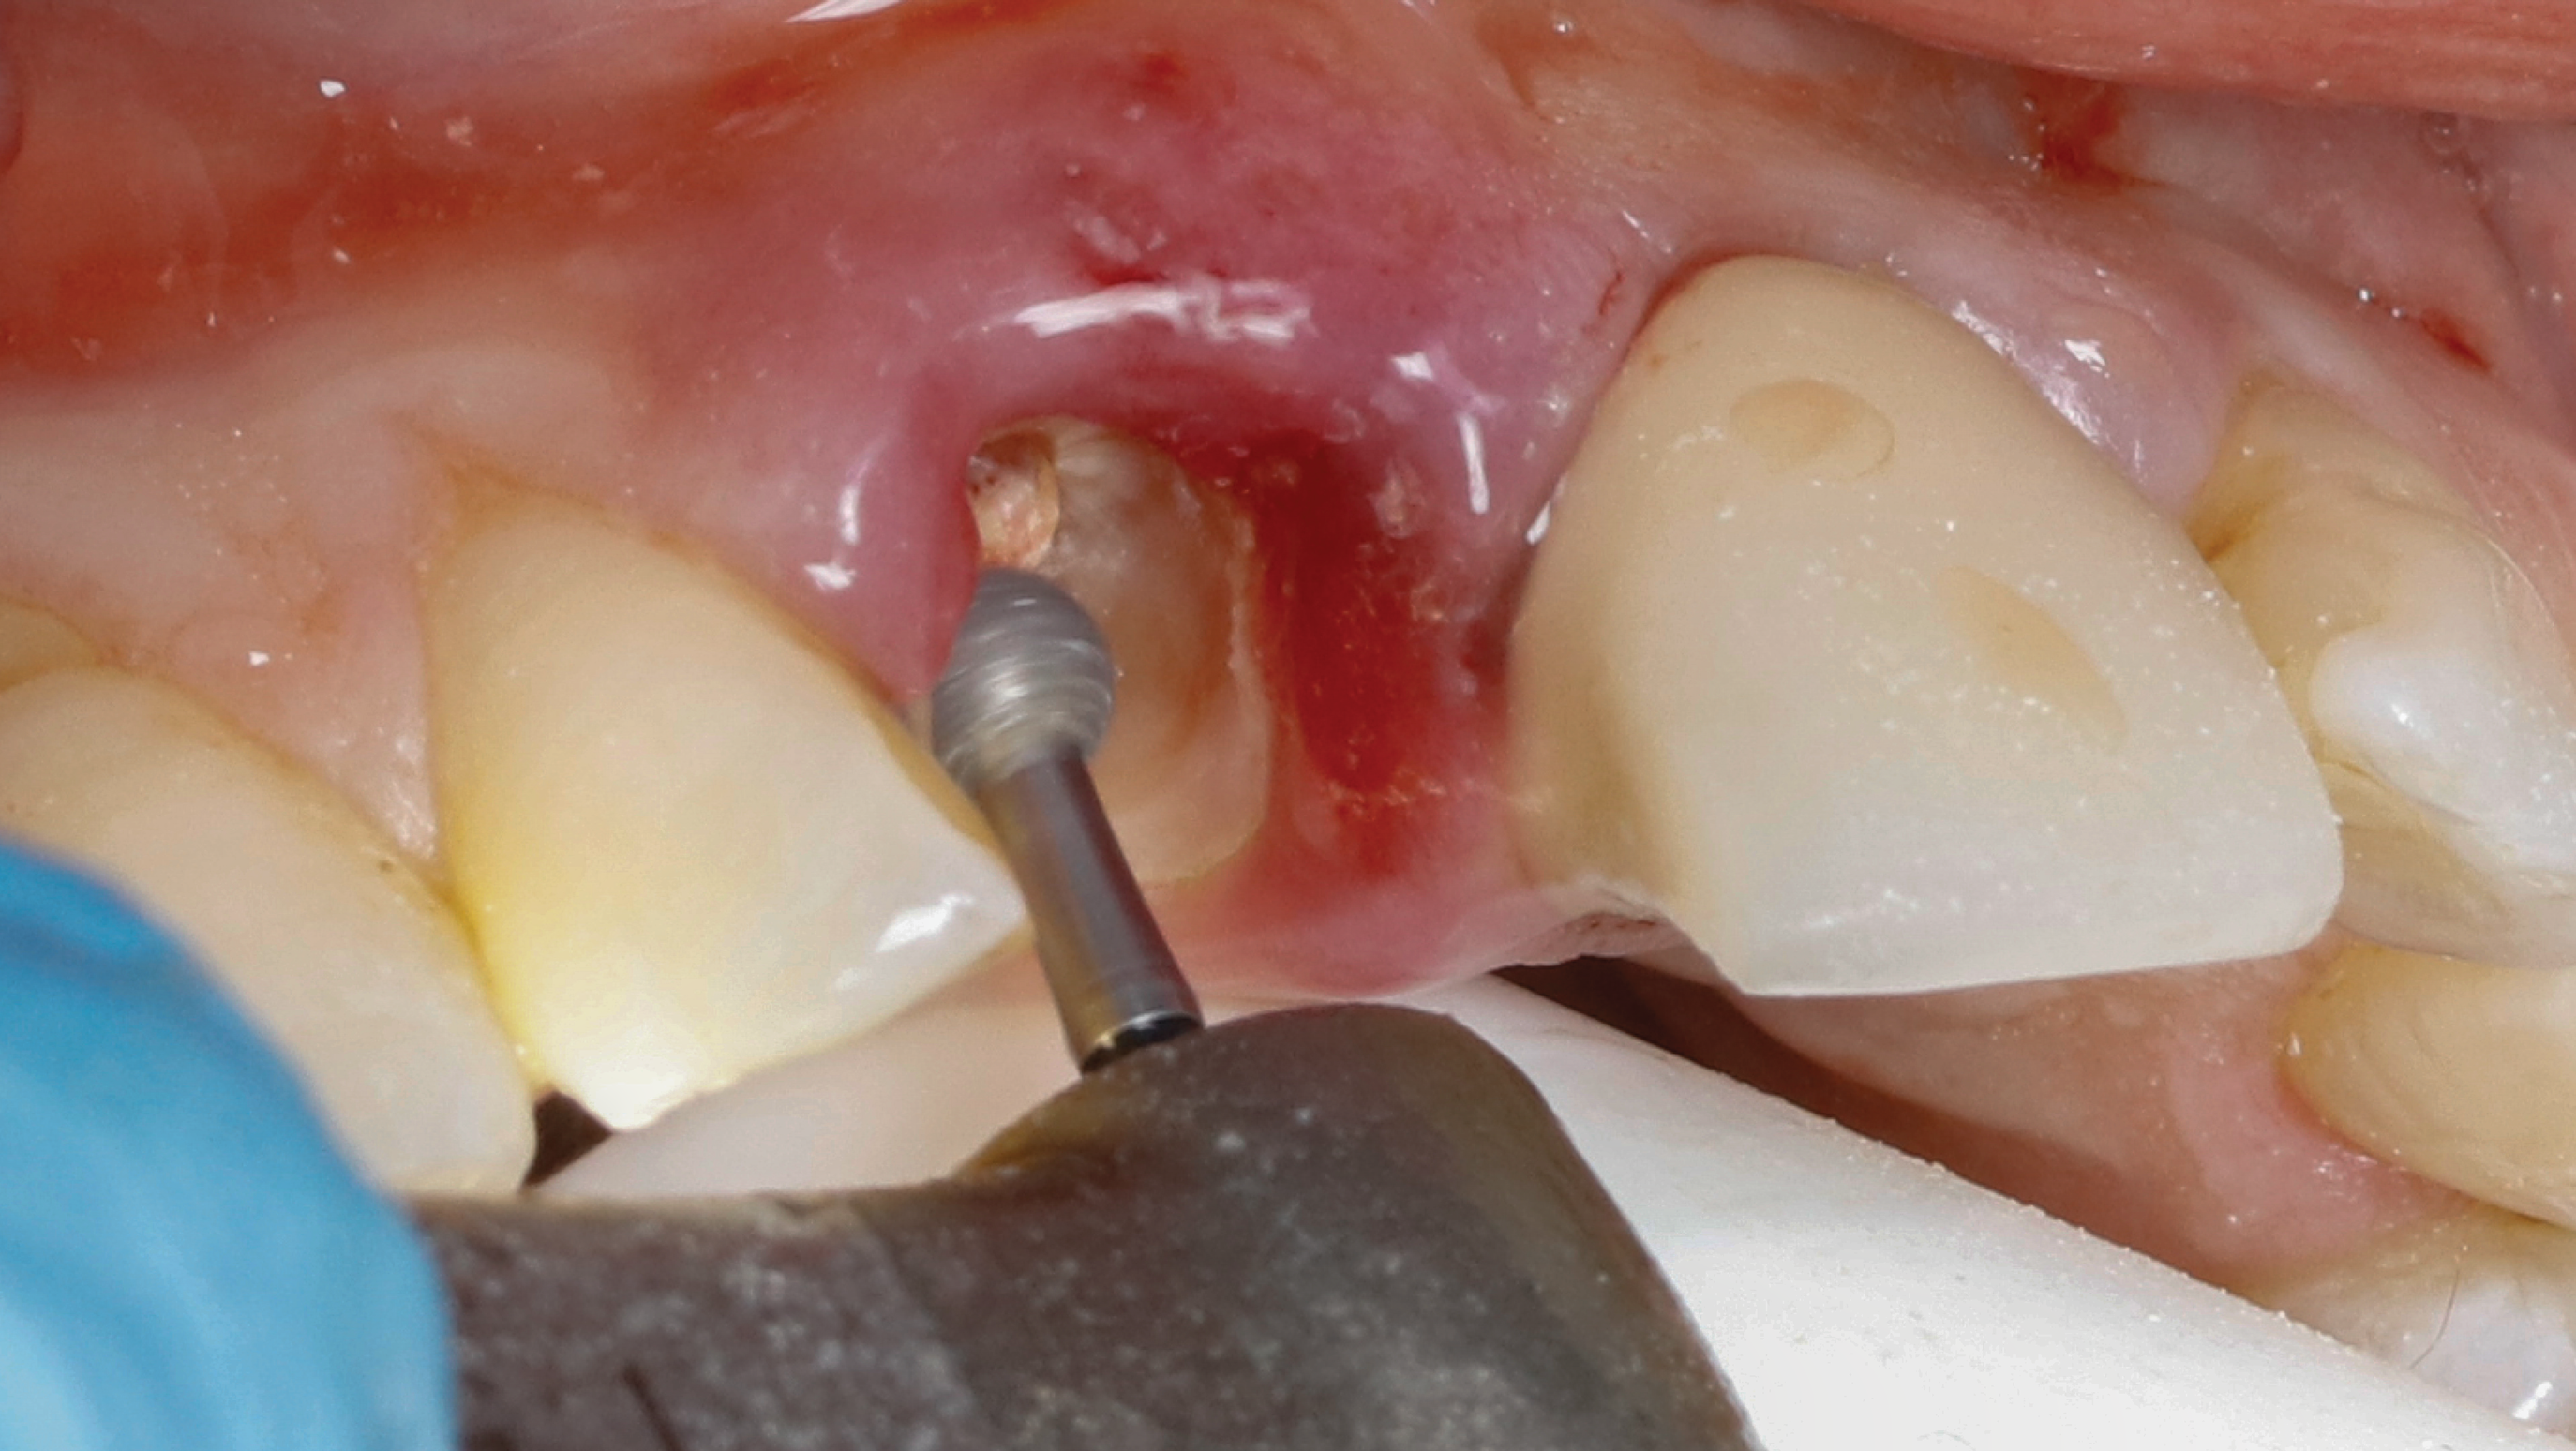

Step 1 - Hollow out the tooth center: A 3-mm diameter round diamond bur (Meisinger 801H-029) is used to hollow out the middle of the tooth 2 mm to 3 mm subgingivally, leaving a 1 mm ring of dentin around the circumference of the root (Figure 5).

Fig 5. SPOT Step 1: After the clinical crown is removed, a high-speed diamond bur (Meisinger 801H-029) is used to hollow out the center of the tooth 2 mm to 3 mm subgingivally leaving a 1 mm rim of dentin around the root circumference.

Figure 5